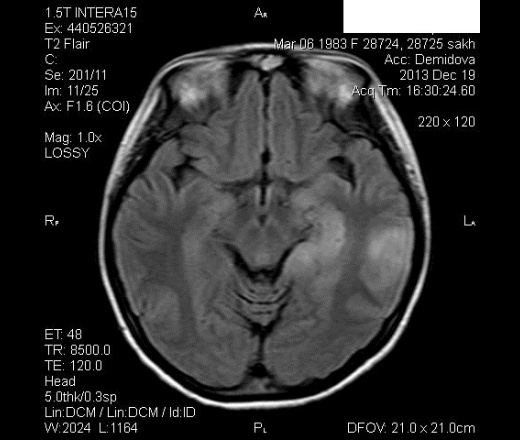

Девушка с жалобами общее недомогание , неоднократные судороги с потерей сознания, нарушение памяти с 16.12.2013г.Травм, операций не было.Проходила МР-исследование 19.12.2013 г и сегодня.

От 19.12.2013г.

Сегодня

Проводили биопсию ( точные данные неизвестны).В направлении от сегодня-рассенный энцефаломиелит.

На глиобластому не похоже?

Не знаю, Дмитрий.Здесь изменения слева и справа.Сначала вообще на энцефалит подумала, дифф. с объемом, а сегодня вон какая штука.И дислокация срединных структур , и узловые образования нарисовались более четко..

Возможно следующее: первичный очаг опухоли в левой теменной доле. Далее - развитие судорог с наличием на первом МРТ постиктальных изменений различной локализации. Далее прогрессия опухоли. Накапливают ли контрастное вещество остальные очаги?

Да, справа накапливает.

На мой взгляд опухоль, на некоторых сканах присутствуют гипоинтенсивные линейные структуры, видимо сосуды.

Чем не метастаз?

Написали метастазы.

Не успел. Согласен с Helios, возможен вариант первично множественной глиомы.

А первично-множественная опухоль может быть?